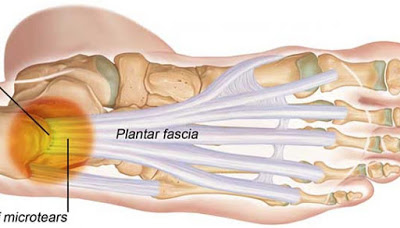

足底筋膜解剖位置與足部受壓力百分比分佈

所以常見疼痛幾乎會在足跟底部後側出現

因足部力量長期拉扯足底筋膜而發炎。

後期也可能產生鈣化、新生骨生成(俗稱骨刺)